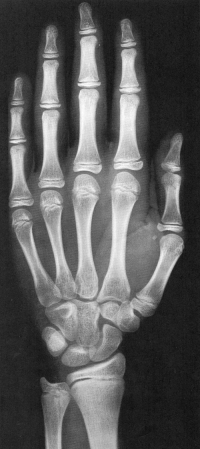

Sexo Masculino

17 anos

18 anos

Fonte: GREULICH, W.W. & PYLE, S.I.: Radiografic Atlas of Development of the Hand and Wrist. Stanford University Press, 2° edition, 1959.